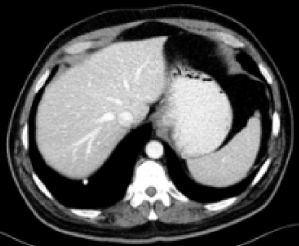

| LDCT (0.7586) | FDCT |

RED-CNN (0.8790)

Figs. 3 and 4 demonstrate precise removal of noise from whole scans as well as specific regions of interest (ROIs), proving the effectiveness of our model over baseline architectures and other self-supervised tasks. As shown, both the RVAE and SSWL are able to quantitatively and qualitatively outperform their respective counterparts.